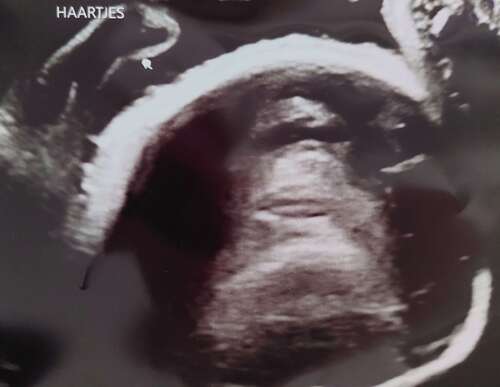

Zie je hier ook haartjes, of kijk ik naar heel iets anders? 馃槅